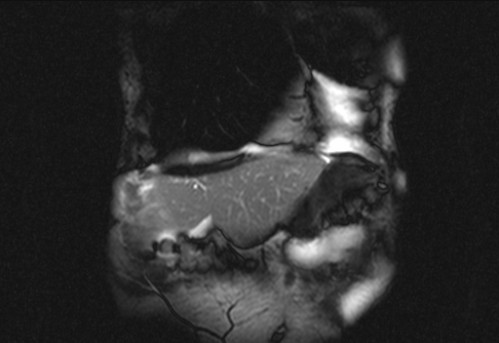

Auffälliges Abdomen bei der Vorsorgeuntersuchung einer älteren Dame

ICD: C64

68 Jahre alte Frau. Sie geht zur Darmspiegelung im Rahmen ihrer Krebsvorsorgeuntersuchung. Der Internist bemerkt bei der ergänzenden sonografischen Untersuchung des Abdomens einen auffälligen Befund.